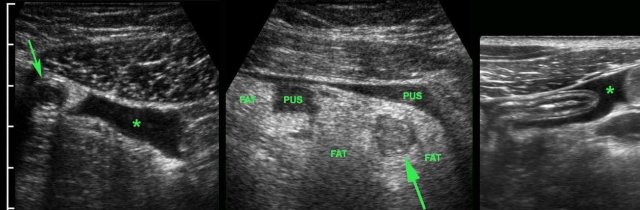

In this patient, US shows large quantities of inflamed fat (*) and the thickened ileum representing successful walling-off of the (imminent) perforation of the appendix (arrow).

Note a calcified fecolith (arrow on CT scan) in the appendix at a higher level.

Patient with a small appendiceal abscess, ventrally walled-off by the ileum.

The appendix (arrows) is small because it has evacuated its purulent contents in to the abscess.

Note the calcified fecolith (arrowhead) on the bottom of the abscess.

Drainage was performed from laterally.

Man of 70 years, with a large abscess in the RLQ.

On CT the appendix could not be identified.

US confirms an inflamed appendix (arrow).